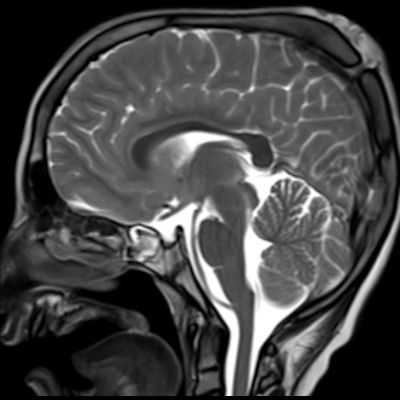

1. A) Kontrastlı FLAIR aksiyel görüntüde ve sagital T2A görüntüde vertekste orta hatta cilt altında dilate tortiyoze vasküler kollateraller (oklar). Paryetal kemikte orta hatta defekt (ok) ve defekt ile ilişkili vasküler yapıların cilt altı yumuşak dokulara uzanımı izlenmektedir.

1. Genellikle çocukluk çağında saptanan, venöz bir malformasyondur. Kafatasının dış yüzeyinde yer alan emisserian venlerin, orta hatta kalvaryal defektten intrakraniyal dural venöz sinüslerle anormal bağlantısı olan, komünikan venöz yapılarla karakterize kranial venöz anomalidir.

2. Genellikle orta hatta yer alır ve yumuşak, valsalva manevrasıyla büyüyebilen bir şişlik olarak kendini gösterir.

3. Lezyon, genellikle süperior sagittal sinüs gibi büyük venöz sinüslerle bağlantı gösterir.

4. Bu bağlantılar kemikteki bir defekt veya ince kortikal pencere yoluyla olur.

5. MRG’de hızlı venöz akıma bağlı “flow void” (sinyal kaybı) alanları gözlenebilir.

6. En tanımlayıcı görüntüleme yöntemi MR venografidir.

7. İntrakraniyal ve ekstrakraniyal venöz yapıların ilişkisi net şekilde gösterilir.

8. Lezyonun süperior sagittal sinüs veya diğer venöz sinüslerle bağlantısı doğrulanır.